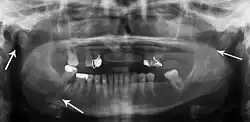

multiple mandible fractures of a patient in the right condyle (extracapsular/neck/not dislocated), right body (vertically unfavourable) and left coronoid process

Panoramic radiographs are tomograms where the mandible is in the focal trough and show a flat image of the mandible. Because the curve of the mandible appears in a 2-dimensional image, fractures are easier to spot leading to an accuracy similar to CT except in the condyle region. In addition, broken, missing or malaligned teeth can often be appreciated on a panoramic image which is frequently lost in plain films. Medial/lateral displacement of the fracture segments and especially the condyle are difficult to gauge so the view is sometimes augmented with plain film radiography or computed tomography for more complex mandible fractures.

Research has shown that panoramic radiography is similar to computed tomography in its diagnostic accuracy for mandible fractures and both are more accurate than plain film radiograph.[12] The indications to use CT for mandible fracture vary by region, but it does not seem to add to diagnosis or treatment planning except for comminuted or avulsive type fractures,[13] although, there is better clinician agreement on the location and absence of fractures with CT compared to panoramic radiography.[14]